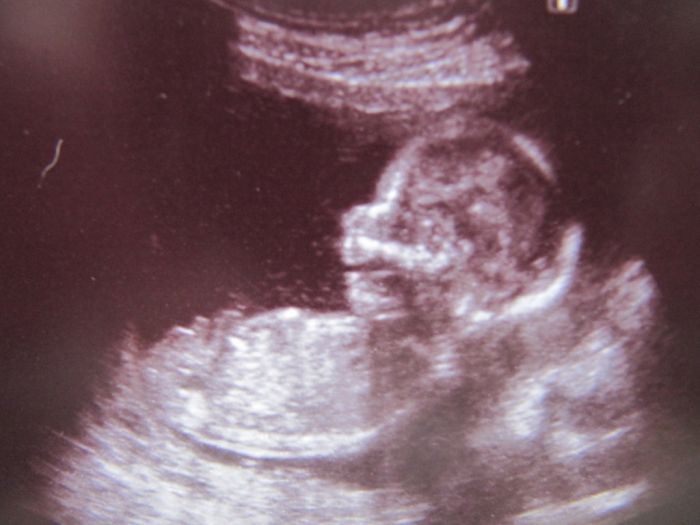

Tak se hlásím po dnešní genetice, zdá se být všechno v naprostém pořádku, tak jsem šťastná jak blecha, teď ještě v tom 20tt., ale věřím, že když dopadlo tohle dobře, tak i ten velký bude v pořádku. Je to definitivní kluk, pan profesor mi udělal i 3 fotky, jako dáreček (bez placení, na pohlaví jsem se neptala-sám se nabídnul, zda to chci vědět). Tak je připojuju, na jedné je z profilu s otevřenou pusinkou, na jedné zepředu-pěkně viditelná čočka v jednom oku a na poslední výbavička našeho frajera.

Marse: na té první to vypadá, jak by se tvůj chlapeček zrovna něčemu chechtal

Leňule, jj, vypadá že se chechtá. A ten velký probíhá přes břicho, tak se partner nemusí obávat